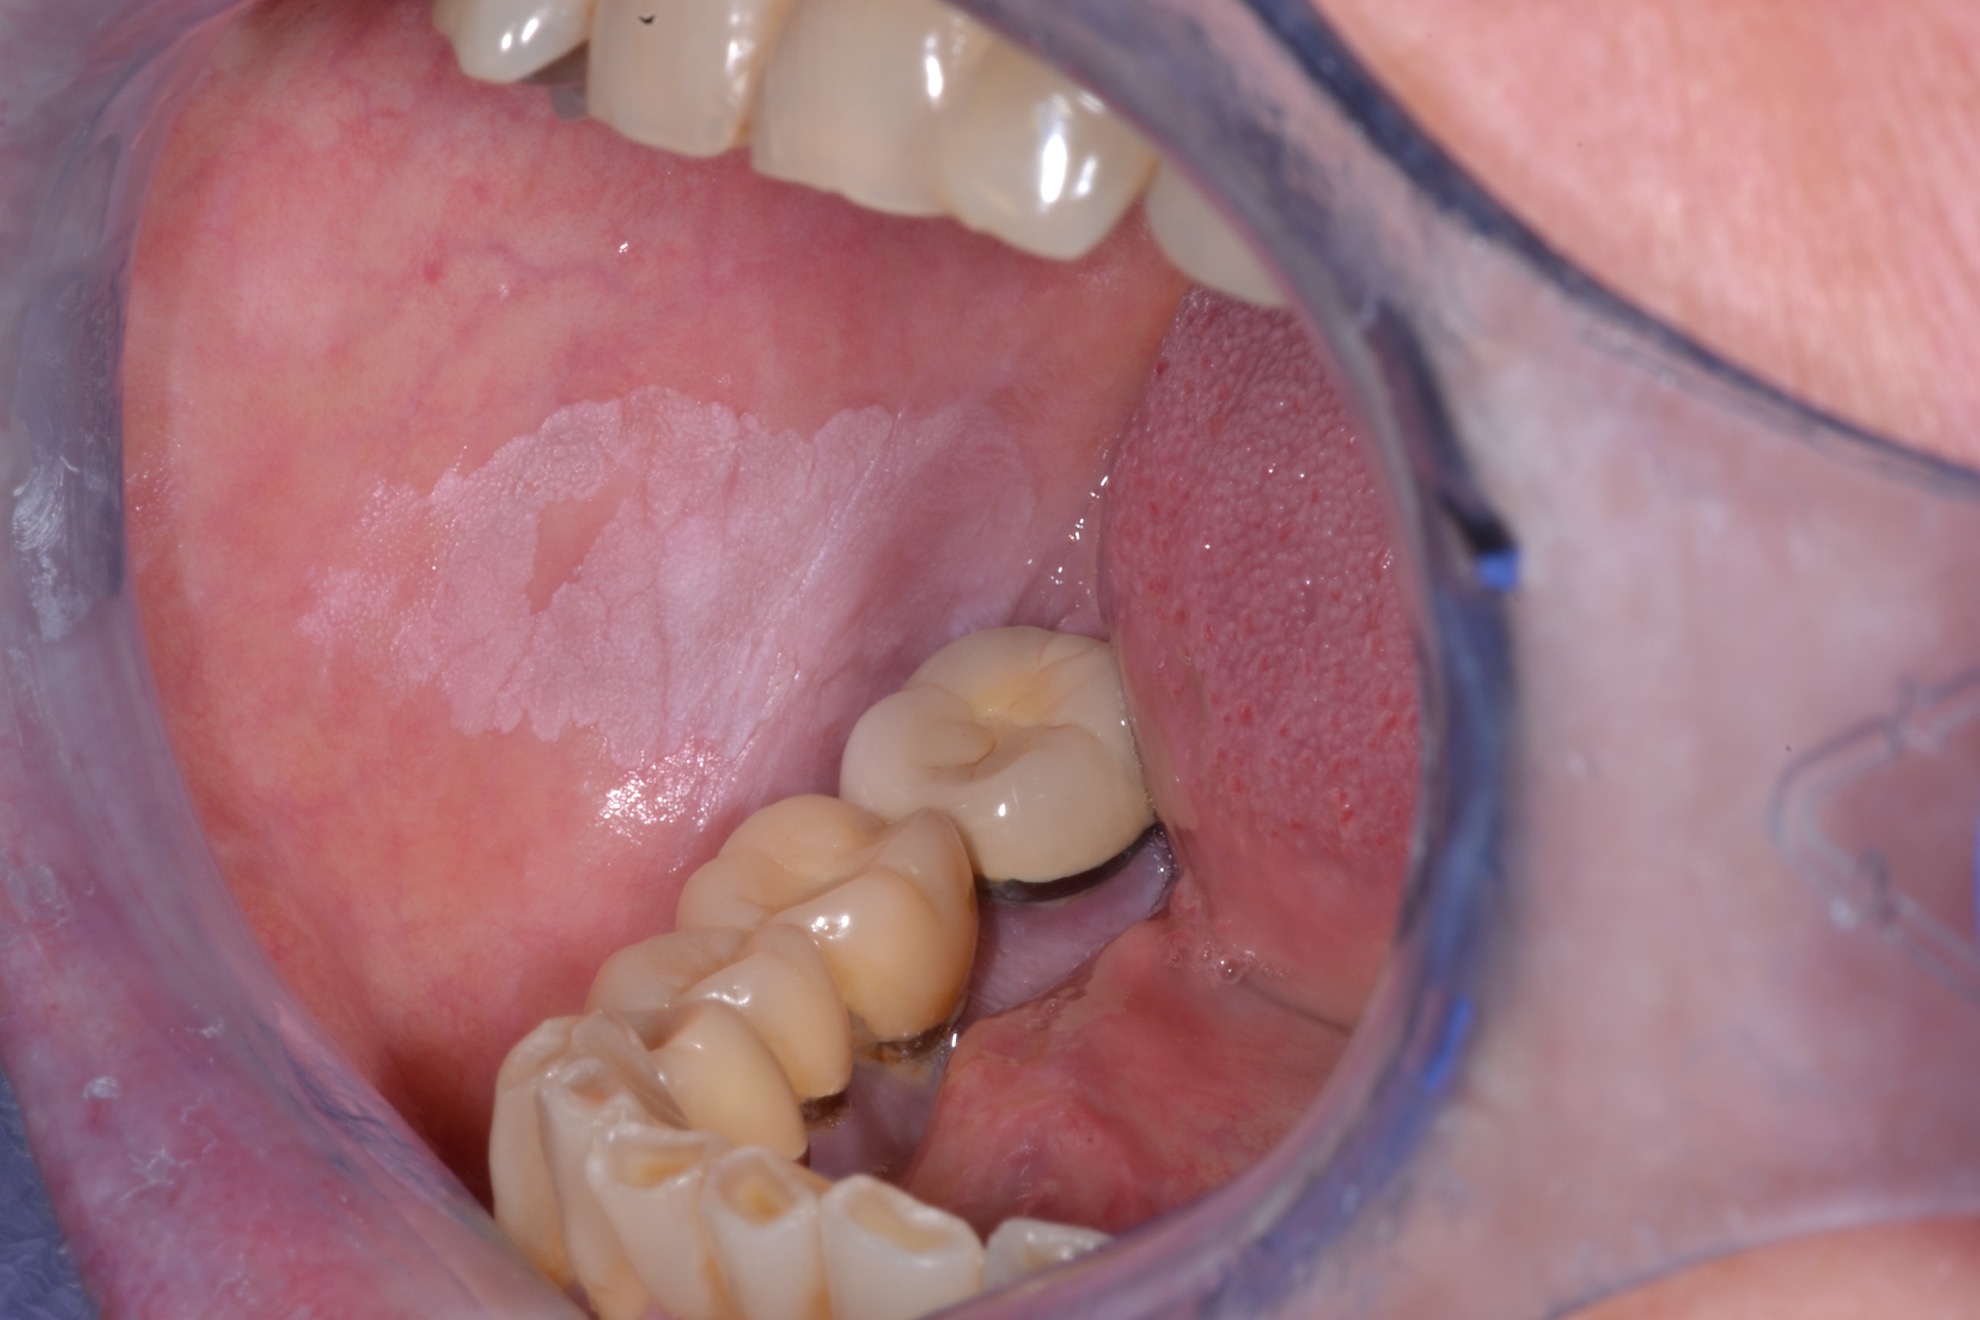

White Spots On Gums Leukoplakia . Leukoplakia is a condition involving thickened white patches on the mucous membranes (lining) of the mouth, gums, and/or. Leukoplakia patches on your tongue, gums, roof of your mouth, or the inside of your cheeks may be: If you accidentally bite the inside of your cheek or burn the roof of your. The patches don’t hurt but they don’t. They may thicken or harden overtime, and they. They are typically harmless, although some doctors think they are precancerous. Leukoplakia describes white patches on the roof of the mouth, tongue, and gums. This mouth condition appears as thick, white patches on the gums, the cheeks and the bottom of the mouth that cannot be scraped. Leukoplakia are small white patches that appear on the gums, the insides of the cheeks, the bottom of the mouth, and the tongue. Leukoplakia is a condition that creates white patches on your tongue, gums or the inside of your cheeks. But not every white patch in the mouth is leukoplakia.

If you accidentally bite the inside of your cheek or burn the roof of your. Leukoplakia describes white patches on the roof of the mouth, tongue, and gums. They may thicken or harden overtime, and they. They are typically harmless, although some doctors think they are precancerous. But not every white patch in the mouth is leukoplakia. Leukoplakia are small white patches that appear on the gums, the insides of the cheeks, the bottom of the mouth, and the tongue. The patches don’t hurt but they don’t. Leukoplakia is a condition involving thickened white patches on the mucous membranes (lining) of the mouth, gums, and/or. This mouth condition appears as thick, white patches on the gums, the cheeks and the bottom of the mouth that cannot be scraped. Leukoplakia is a condition that creates white patches on your tongue, gums or the inside of your cheeks.

White Spots On Gums Leukoplakia Leukoplakia patches on your tongue, gums, roof of your mouth, or the inside of your cheeks may be: Leukoplakia patches on your tongue, gums, roof of your mouth, or the inside of your cheeks may be: This mouth condition appears as thick, white patches on the gums, the cheeks and the bottom of the mouth that cannot be scraped. If you accidentally bite the inside of your cheek or burn the roof of your. Leukoplakia describes white patches on the roof of the mouth, tongue, and gums. Leukoplakia are small white patches that appear on the gums, the insides of the cheeks, the bottom of the mouth, and the tongue. The patches don’t hurt but they don’t. But not every white patch in the mouth is leukoplakia. They may thicken or harden overtime, and they. They are typically harmless, although some doctors think they are precancerous. Leukoplakia is a condition involving thickened white patches on the mucous membranes (lining) of the mouth, gums, and/or. Leukoplakia is a condition that creates white patches on your tongue, gums or the inside of your cheeks.